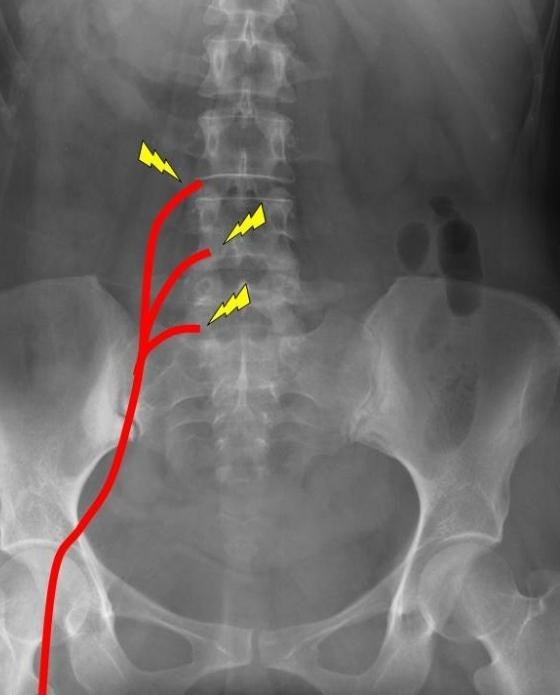

Седалищные нервы крупные и длинные. Они расположены по бокам поясницы, проходят до пальцев ног, иннервируют не только позвоночные структуры, но и органы малого таза. Поэтому защемление нервных корешков приводит к нарушению их работы. Это ускоряет диагностику патологии, позволяет быстро приступить к проведению лечения.

Ущемление седалищного нерва может быть спровоцировано формированием воспалительного отека, стойким мышечным спазмом. Но наиболее часто сдавление происходит при смещении острого костного нароста (остеофита) или поясничного межпозвонкового диска.

При ущемлении седалищного нерва возникает жгучая, колющая, пронизывающая боль. Она не четко локализована, а распространятся по ходу нерва, иррадиирует в бедра, голени, ягодицы. Если сдавление сопровождается воспалением, то боли становятся хроническими. Их усиление происходит при переохлаждении, остром переживании стрессовой ситуации, повышенной физической нагрузке, обострении других патологий.

Защемление всегда сопровождается расстройствами чувствительности. При ее усилении ощущается покалывание, ползание мурашек, при ослаблении — онемение. Нередки и вегетативные нарушения. Из-за сильных болей потеют стопы, отекает и краснеет кожа.